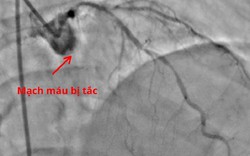

• Sau chuỗi ngày liên hoan, dọn nhà đón Tết, người phụ nữ phải cấp cứu khẩn

Sau chuỗi ngày liên hoan, dọn nhà đón Tết, người phụ nữ phải cấp cứu khẩn

Sức khỏe -

Tưởng chỉ là mệt mỏi sau chuỗi ngày liên hoan, dọn dẹp nhà cửa chuẩn bị đón Tết, một phụ nữ Lạng Sơn suýt phải trả giá bằng sức khỏe và tính mạng.